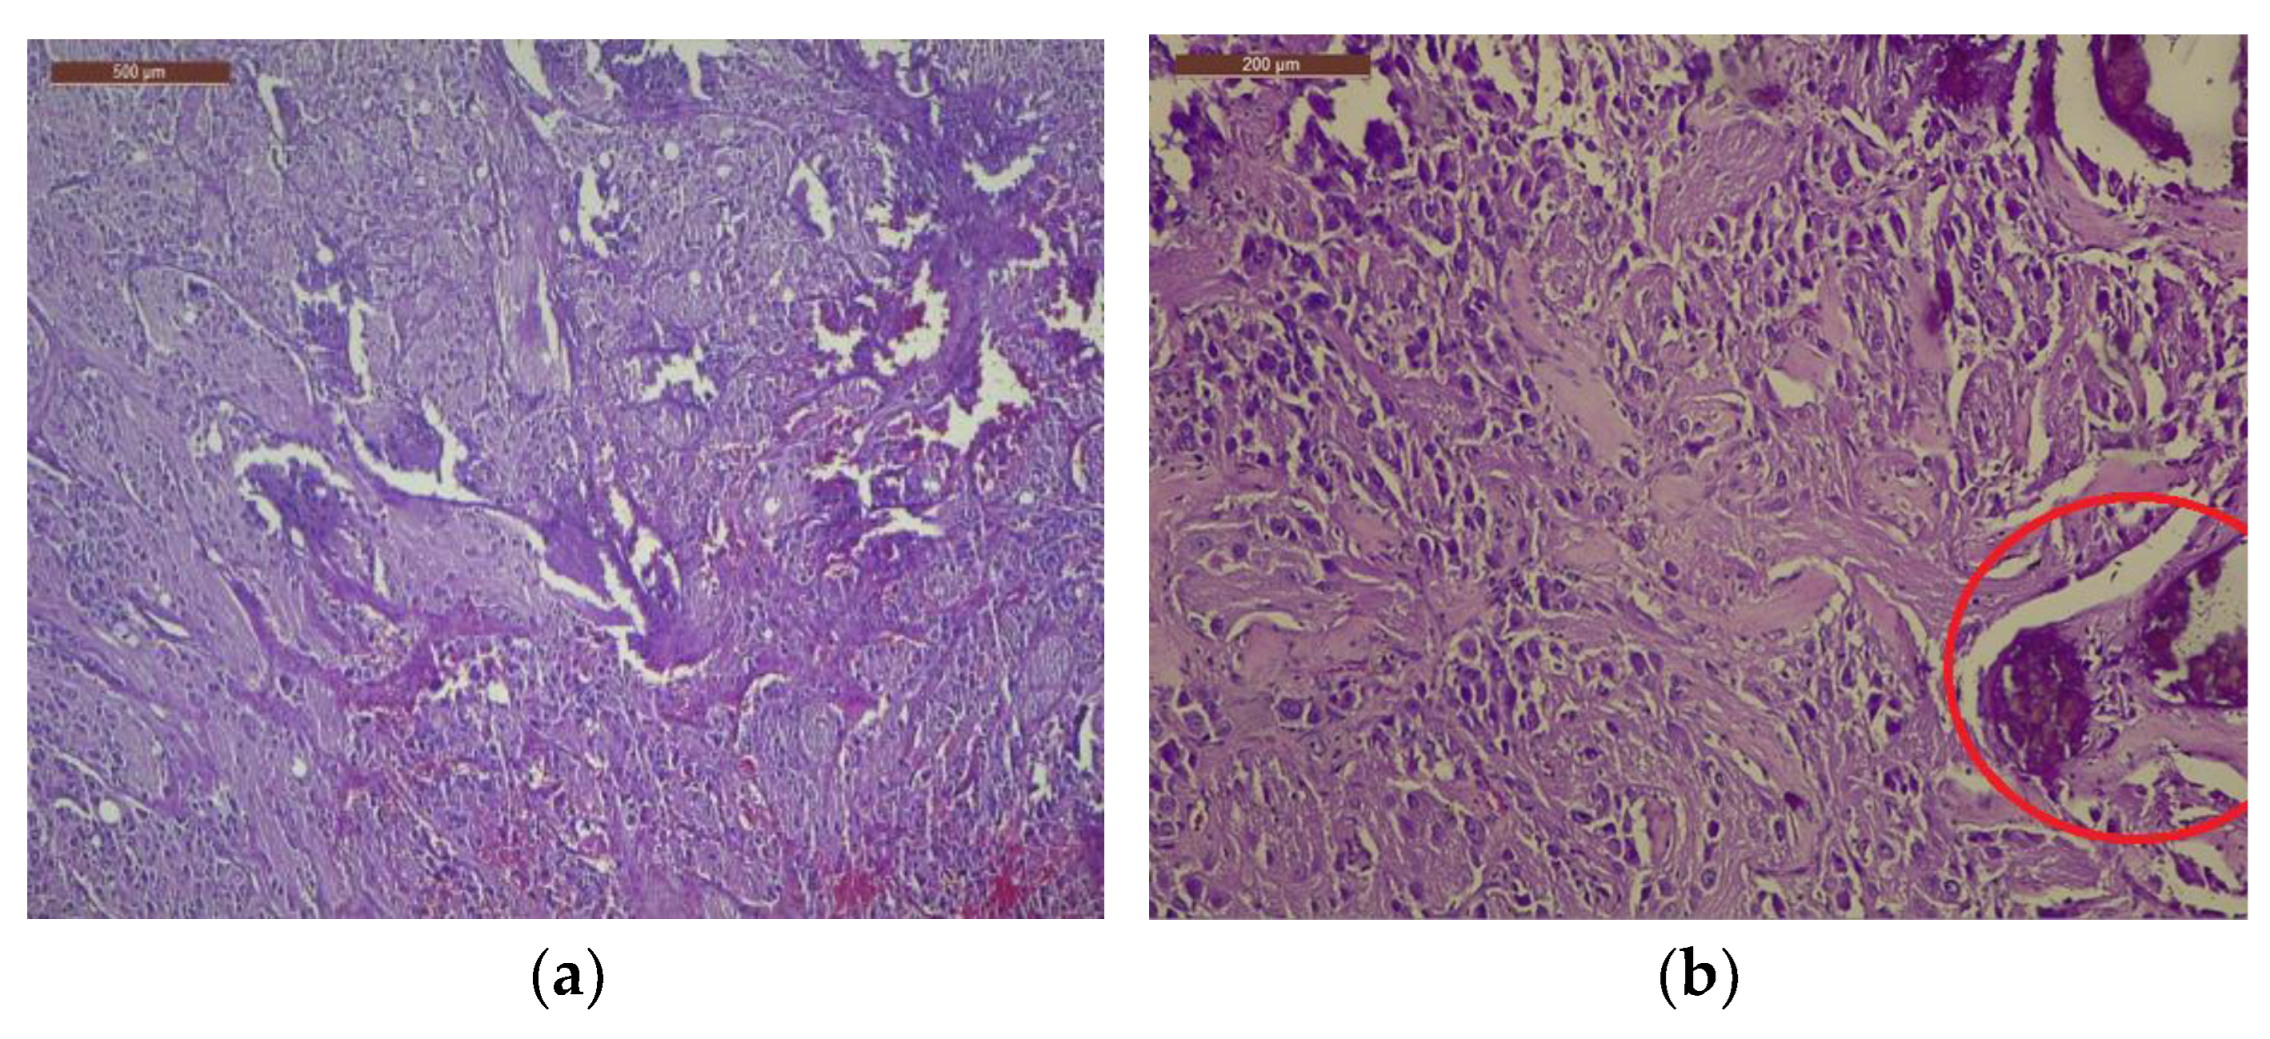

The tumor was histologically determined to be an INSS II-localized ganglioneuroblastoma intermixed with a stroma-rich (Shimada Classification) tumor with complete gross excision, positive lymph nodes, and a low MKI (mitosis-karyorrhexis index) of less than 100. The growth pattern of the tumor was solid/lobular. Large, round-to-ovoid nuclei and an abundance of basophilic cytoplasm were features of the tumor cells. A “salt and pepper appearance” with prominent nucleoli and alternate regions of euchromatin and heterochromatin was seen. Other tumor cells were distinguished by rich, eosinophilic cytoplasm, eccentric nuclei, and prominent cell boundaries. The tumor cells contained a small quantity of bleeding and had somewhat calcified dystrophic regions (Figure 4).

Figure 4.

Visualization of tumor cell nuclei characterized by conspicuous enlargement, accompanied by discernible nucleoli and cytoplasm exhibiting a dense eosinophilic nature: (a) Within the tumor cell population, minor regions of hemorrhage have been noted, 4× magnification; (b) observe the tumor’s growth pattern displaying either lobular or solid arrangements, accompanied by notable instances of dystrophic calcification, 10× magnification. The examination was performed using H&E staining. H score for NSE = 235, NF200 = 230, S100 = 298, GFAP = 288.

Additional immunohistochemistry testing was conducted using the following panel of markers to confirm the final diagnosis and rule out other lesions with a similar appearance: Chromogranin, Neurofilament (NF 200), Protein S 100 (S100), Glial Fibrillary Acidic Protein (GFAP), Neutron-Specific Enolase (NSE), Synaptophysin, and T-Cell Surface Glycoprotein E2 (CD99). As an internal control marker, vimentin showed a favorable stromal response. The tumor cells responded moderately to strongly to NSE, Synaptophysin, and NF 200. The distribution of the cytoplasmic response pattern was diffuse and heterogeneous. In the ganglion cells and the stroma, immunohistochemistry for S100 and GFAP was highly reactive. S100 was also present in the cytoplasm of Schwann cells. Chromogranin was found to be isolated positively in neuroblasts. Overall, CD99 was rated as unfavorable (Figure 5).

(a) Protein S100 demonstrated a robust and positive response in both Schwann cells and ganglion cells; (b) tumor cells exhibited a strong NSE expression, characterized by a cytoplasmic pattern of reactivity; (c) notably, tumor cells displayed a marked, widespread, and relatively uniform NF 200 expression; (d) GFAP demonstrated a moderate to strong positive expression in the ganglion cells. The magnification for the specimen was ×4.